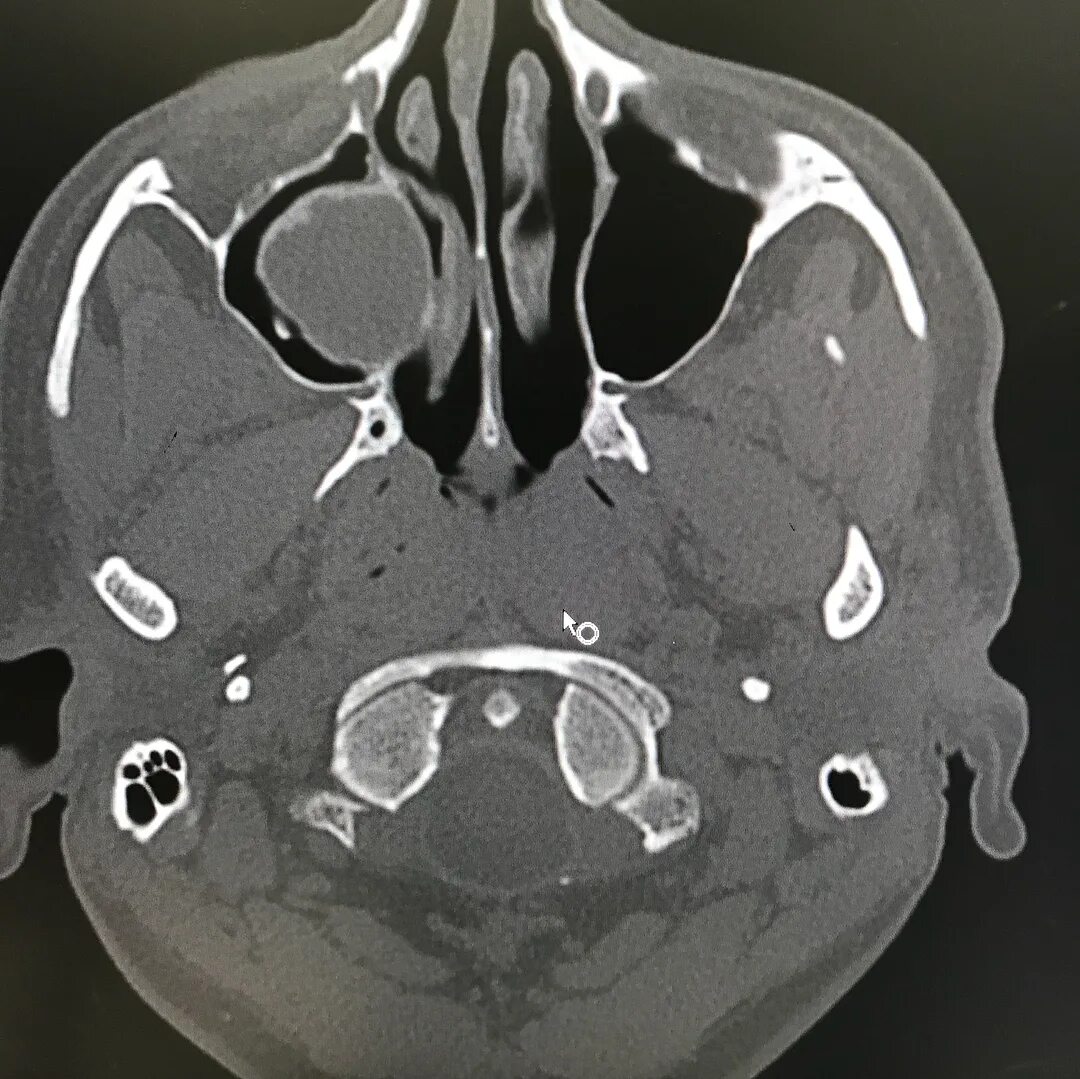

50 лет кт